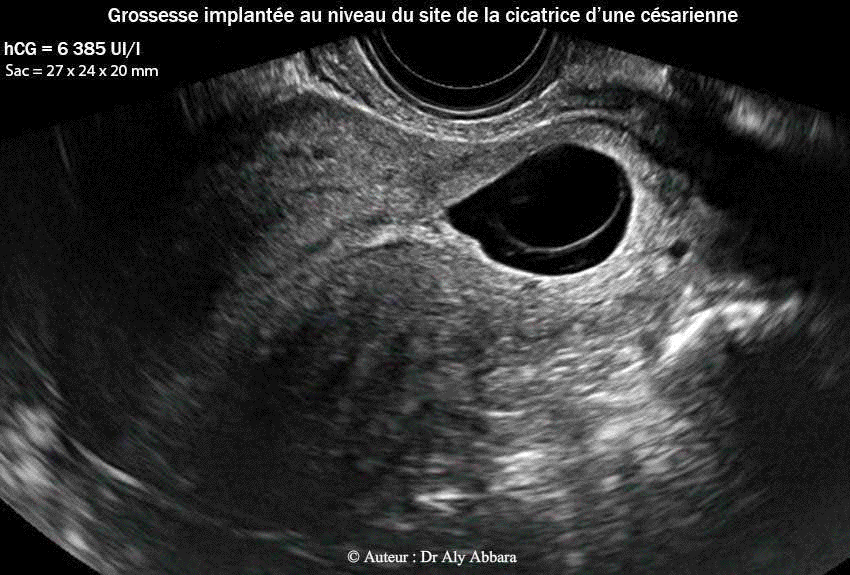

• Images échographiques par voie endovaginale montrant un sac gestationnel d'une grossesse débutante et partiellement intramurale, implantée dans le site de la cicatrice de l'hystérotomie segmentaire transversale d'une ancienne césarienne.

• L'aspect du sac gestationnel au 4e semaine post traitement médical par méthotrexate : il mesure 27 x 24 x 20 mm de diamètres (= 6,7 cm3) ; le dosage de β-hCG plasmatique était égal à 6385 UI/l.

• A ce stade de l'évolution du sac gestationnel, le tissu trophoblastique envahit la paroi antérieure de la zone isthmique de l'utérus et devint en contact avec la paroi vésicale contiguë ; on note aussi la mise en évidence de microvaisseaux naissant au niveau du trophoblaste et pénétrant verticalement dans la paroi vésical juxtaposée (trophoblaste percreta).

31.10.2012 = (J27) = 3+6 S 6 385 UI/l 27 x 24 x 20 mm = 6,7 cm3 J0